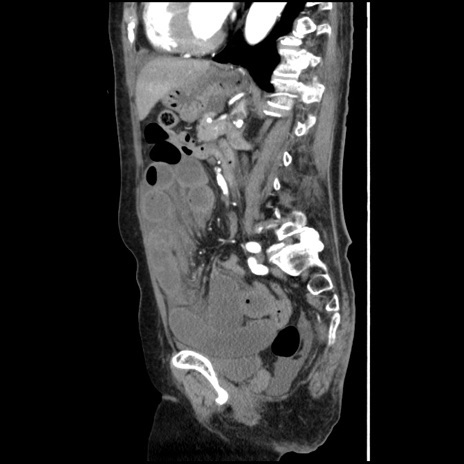

症例1(矢状断像)

【症例】80歳代女性

【主訴】腹痛

【現病歴】8時間前から腹痛あり来院。

【既往歴】糖尿病、脂質異常症、子宮体癌にて子宮全摘術

【身体所見】意識清明・会話良好だが腹痛で苦悶様、全腹部にわたって反跳痛と圧痛あり

【データ】WBC 13600、CRP 0.14、LDH 224、CK 90